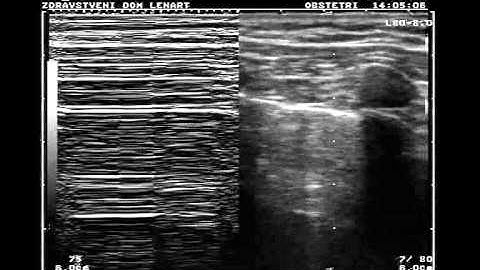

PoCUS Lung - Pneumothorax/Lung Point